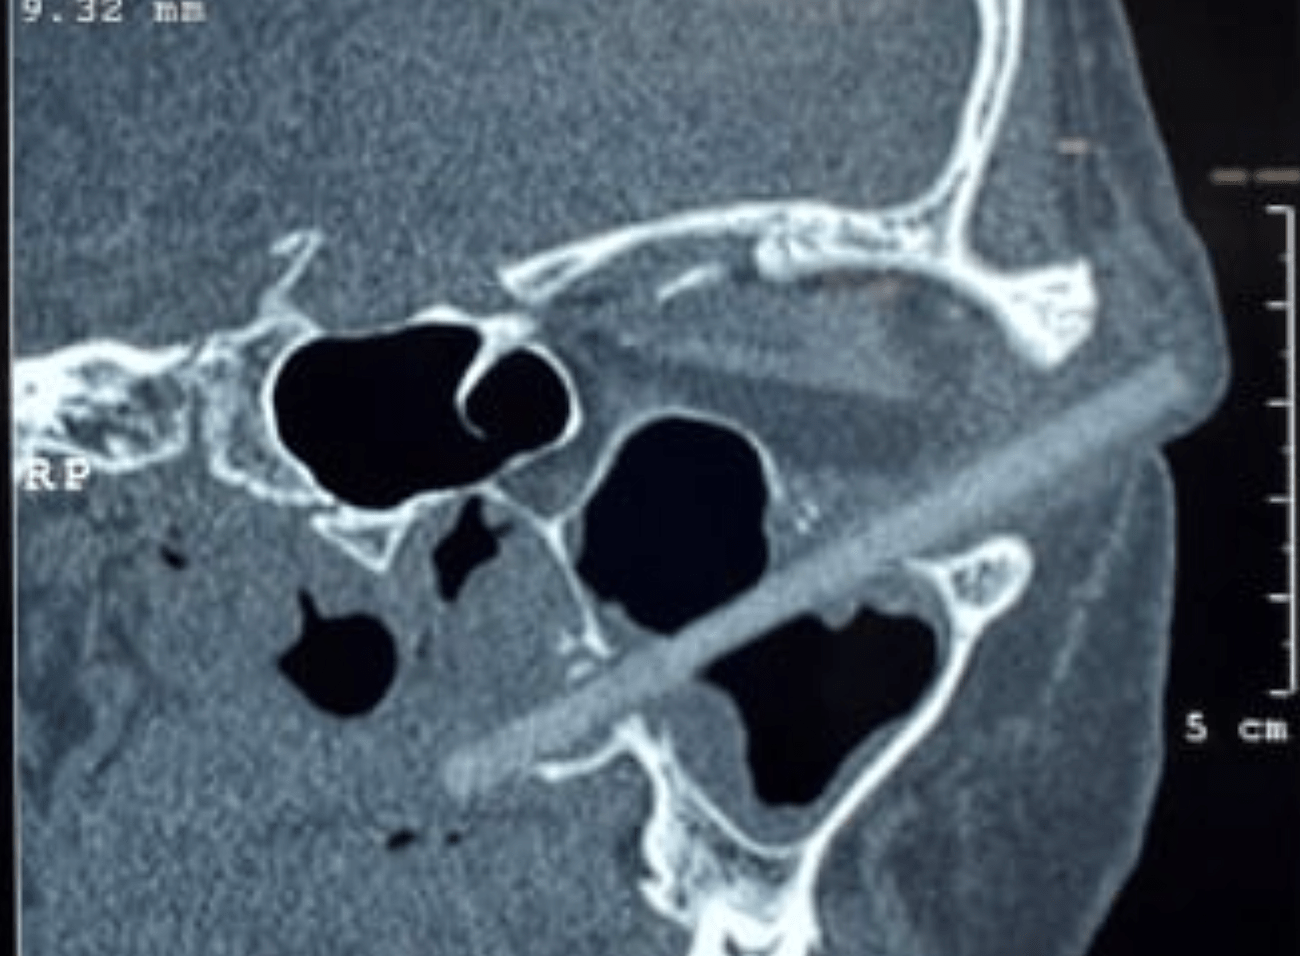

A 24-year-old fellow turned up at Vietnam's Can Tho University of Medicine complaining of swelling and intense pain in one of his eyes. The man claimed that he was previously examined at a medical facility near his home but they couldn't find anything wrong.

Th Can Tho physicians confirmed the man's visio…